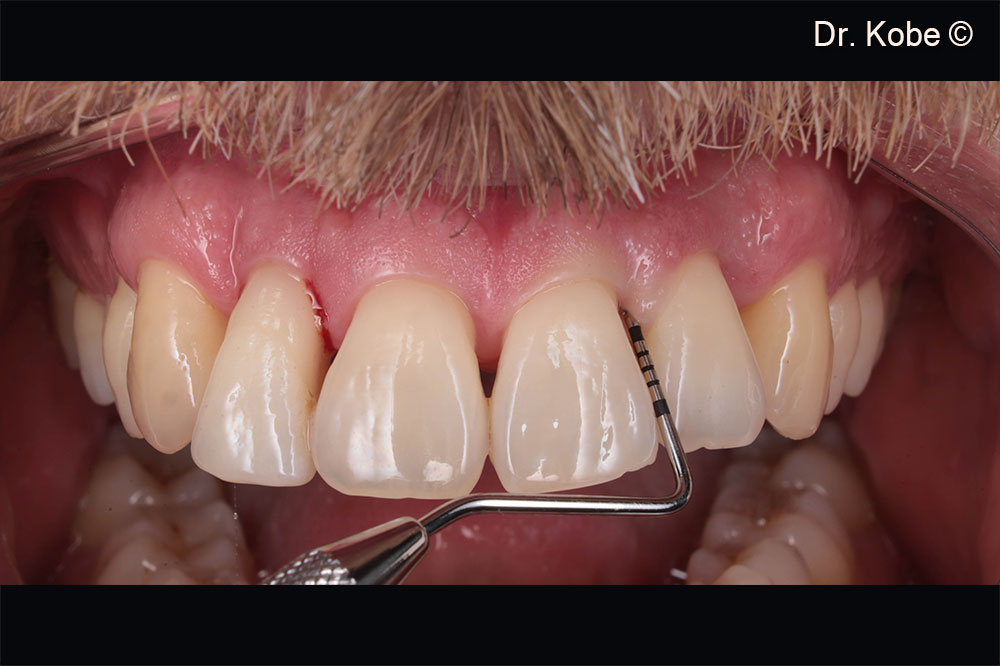

Initial situation

A male patient (40 years old) shows a deep periodontal defect

Initial situation in the first quadrant